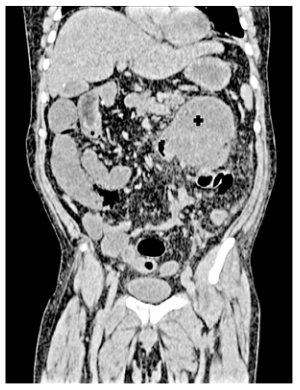

Paciente masculino de 57 años, sin antecedentes familiares de cáncer, que inició su cuadro siete días antes de su ingreso, con dolor abdominal de inicio súbito en cuadrantes abdominales superiores, referido de carácter difuso y de intensidad moderada, tipo cólico, puntuado 7/10 en la escala numérica verbal, que se acompaña de náuseas sin desencadenar vómito, niega fiebre, diarrea o algún otro antecedente relevante, el paciente evoluciona con aumento progresivo del dolor y presencia de escalofríos, motivo por el cual acude a evaluación hospitalaria. En la exploración física se encuentra con presión arterial de 125/75 mmHg, frecuencia cardíaca de 105 lpm, 20 respiraciones por minuto, temperatura de 36.5 °C, abdomen semigloboso, ausencia de peristalsis, con dolor a la palpación superficial y profunda generalizado, con predominio en mesogastrio, resistencia involuntaria, con signo de descompresión positiva. El resto del examen general sin alteraciones. El análisis de sangre de urgencias mostró glucosa 209 mg/dL, creatinina 0.97 mg/dL, proteína total 4 gr/dL, albúmina 2 gr/dL, fosfatasa alcalina 49.8 UI, deshidrogenasa láctica 204 UI, bilirrubina total 1.4 mg/dL, bilirrubina directa 1.08 mg/dL, bilirrubina indirecta 0.32 mg/dL, sodio 140 mmol/L, potasio 3.9 mmol/L, hemoglobina 14.2 gr/dL, hematocrito 45.4%, glóbulos blancos 11.4 k/uL, plaquetas 231 k/uL, TP 17, TPT 24.7, INR 1.33, Se realiza una tomografía computarizada (TC) simple, que muestra una imagen ovoide con bordes regulares y bien definidos de 113 x 89 x 104 mm con contenido heterogéneo en la región inferior del páncreas y anterior al riñón izquierdo. No fue posible identificar la dependencia de órganos del tumor (figuras 1 y 2).

La tomografía axial computarizada muestra lesión tumoral en colon transverso (cruz negra)

La tomografía computarizada corte coronal muestra lesión tumoral en colon trasverso (cruz negra)